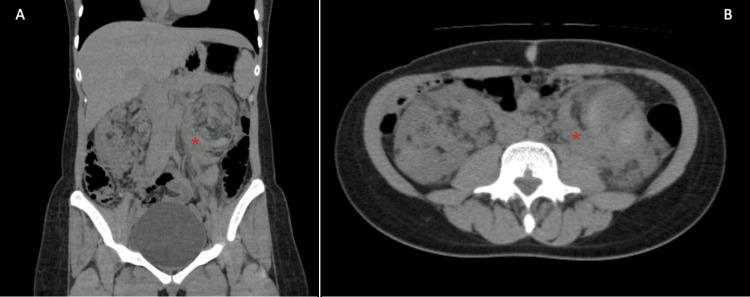

Wunderlich syndrome (WS) is a rare, potentially life-threatening medical condition characterized by spontaneous renal or perinephric hemorrhage occurring in the absence of known trauma. WS usually presents as Lenk's triad: acute flank pain, flank mass sensation, and hypovolemic shock; however, the presentation of this condition can vary in terms of symptom type and duration. We present the case of a 23-year-old previously healthy woman who consulted our emergency department with an unusual subacute form of presentation of WS (eight days of pain) due to an angiomyolipoma. Considering that the patient was clinically stable, a conservative approach with strict follow-up with serial computed tomography scans was taken.

温德利希综合征(WS)是一种罕见的、可能危及生命的医学病症,其特征是在无已知创伤的情况下发生自发性肾或肾周出血。WS通常表现为伦克三联征:急性胁腹痛、胁腹肿块感和低血容量性休克;然而,这种病症的表现会因症状类型和持续时间而有所不同。我们报告一例23岁既往健康的女性病例,该患者因血管平滑肌脂肪瘤以一种不寻常的亚急性形式(疼痛8天)就诊于我院急诊科。鉴于患者临床稳定,采取了保守治疗方法,通过系列计算机断层扫描进行严格随访。